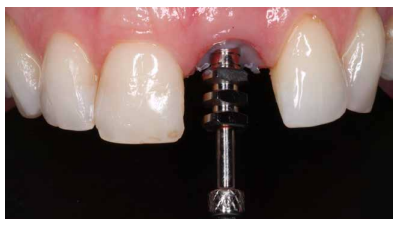

Los beneficios de la carga inmediata incluyen una reducción notable de las intervenciones quirúrgicas, una menor dilatación temporal del tratamiento e incluso un mejor bienestar psicológico y social para el paciente. En casos con importante compromiso estético, la carga inmediata o la provisionalización inmediata, añadida a la colocación inmediata postextracción del IOI permiten minimizar las alteraciones derivadas de la pérdida dental, manteniendo el perfil de emergencia, contorno de tejidos blandos y las papilas gingivales5-7.

Así mismo, se han establecido diferentes protocolos para el manejo del sector estético anterosuperior, que se suman al acto de la colocación inmediata del implante y la corona provisional, donde se incluyen la colocación de un material no reabsorbible entre el IOI y la cortical vestibular para minimizar el posible colapso, así como el manejo de los tejidos blandos periimplantarios8-11.